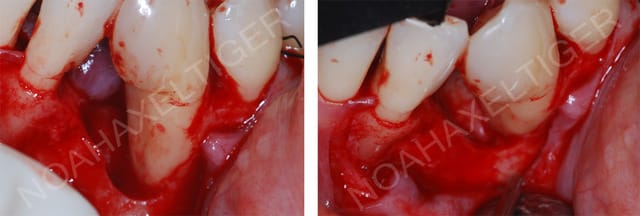

noahaxeltiger-olivier

19/09/2009 à 21h28

mac écrivait:

-------------

> olivier qu'appelles tu lésion infra-osseuse large?

Ca :

Lesion infra osseuse large sr8fpe - Eugenol